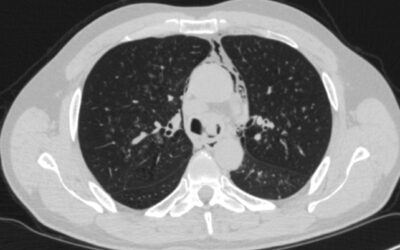

Laser resection of adenocarcinoma of the tracheal bifurcation.A 55-year-old male patient was referred by an oncologist for diagnostic bronchoscopy with biopsy. Chest CT (16.09.2024) demonstrated an endobronchial mass lesion in the tracheobronchial angle region....